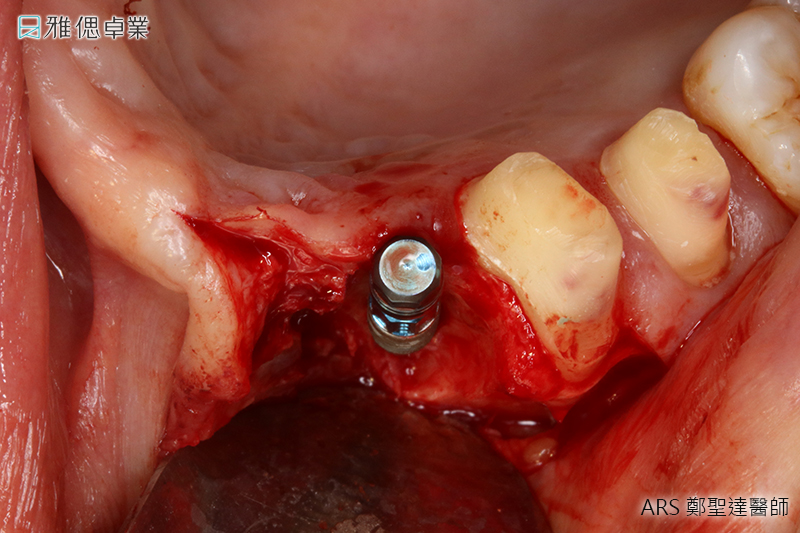

水雷射植牙手術

傳統的雷射植牙會有灼熱感,然而雅偲引進先進的水雷射科技微創植牙,不必縫合傷口,在整個治療過程中將傷口範圍縮小,讓患者感受更加舒適,更大幅度降低術後腫脹疼痛等不舒適感,也可以減少患者害怕開刀的心理負擔。

- 微創治療傷口更小,出血更少

- 精確及精緻切割,組織傷害更少

- 水雷射的生物刺激特性促進骨細胞分裂增生

- 促進微血管及淋巴組合,舒緩術後腫脹

- 水雷射具備的殺菌效果,降低感染機率,增加植牙成功率